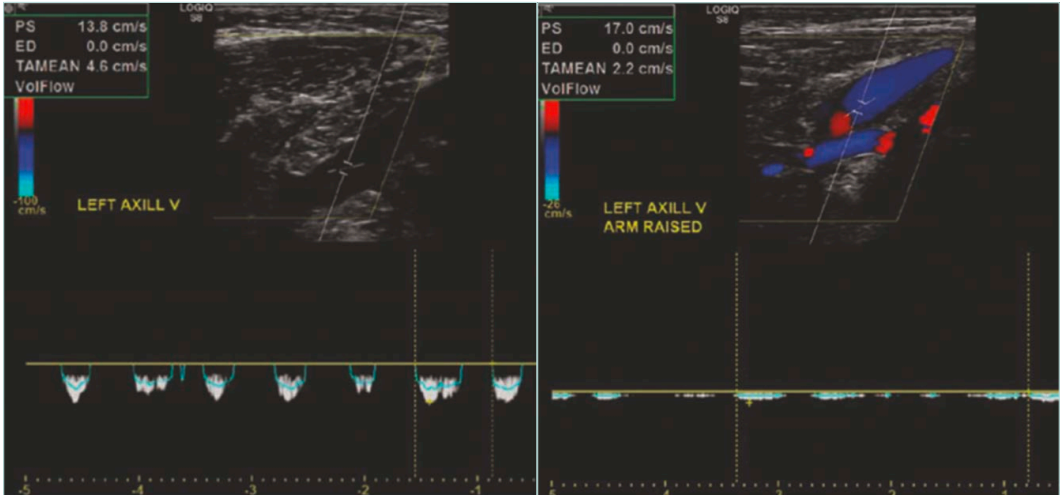

Duplex ultrasound

DUS is a primary, noninvasive modality and the initial imaging test of choice in suspected VTOS. A standard venous DUS may miss the diagnosis if performed only in the neutral position. Therefore, a comprehensive dynamic DUS is essential. This entails examining the axillary-subclavian vein in both neutral and provocative positions, such as with the arm abducted, elevated, or placed in military brace posture. The dynamic scan assesses for the following: i) positional compression with loss or reduction in venous waveform phasicity (Figure 6); ii) retrograde flow or cessation of flow in abduction; iii) visualization of thrombus, echogenic webs, or wall thickening; and iv) presence of prominent collaterals.

Figure 6. Presence of respiratory phasicity in the spectral wave of the axillary vein in the neutral position (left image) and loss of the respiratory phasicity in the abduction position (right image).

Dynamic DUS is operator-dependent and must be interpreted with care. Its sensitivity for detecting acute thrombosis is high, but its ability to assess external compression hinges on precise positioning, patient cooperation, and real-time visualization. High-resolution probes and color Doppler enhancement improve diagnostic yield.